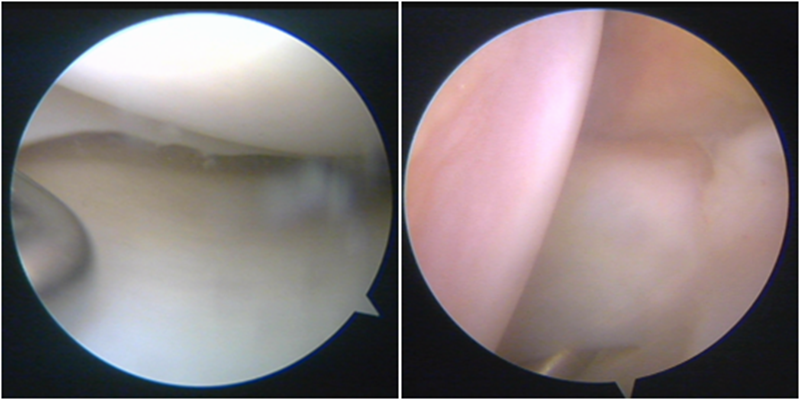

镜下显示ACL残束

内侧半月板

外侧半月板